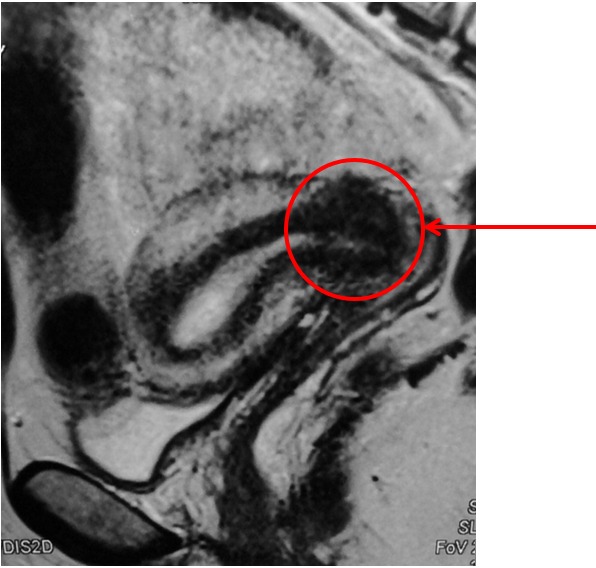

- Магнитно-резонансной томография (МРТ) органов малого таза; (рис 4.)

Рис. 4 МР-признаки опухоли шейки матки

Данные выполненных исследований позволяют установить стадию рака шейки матки и определить индивидуальную тактику лечения.